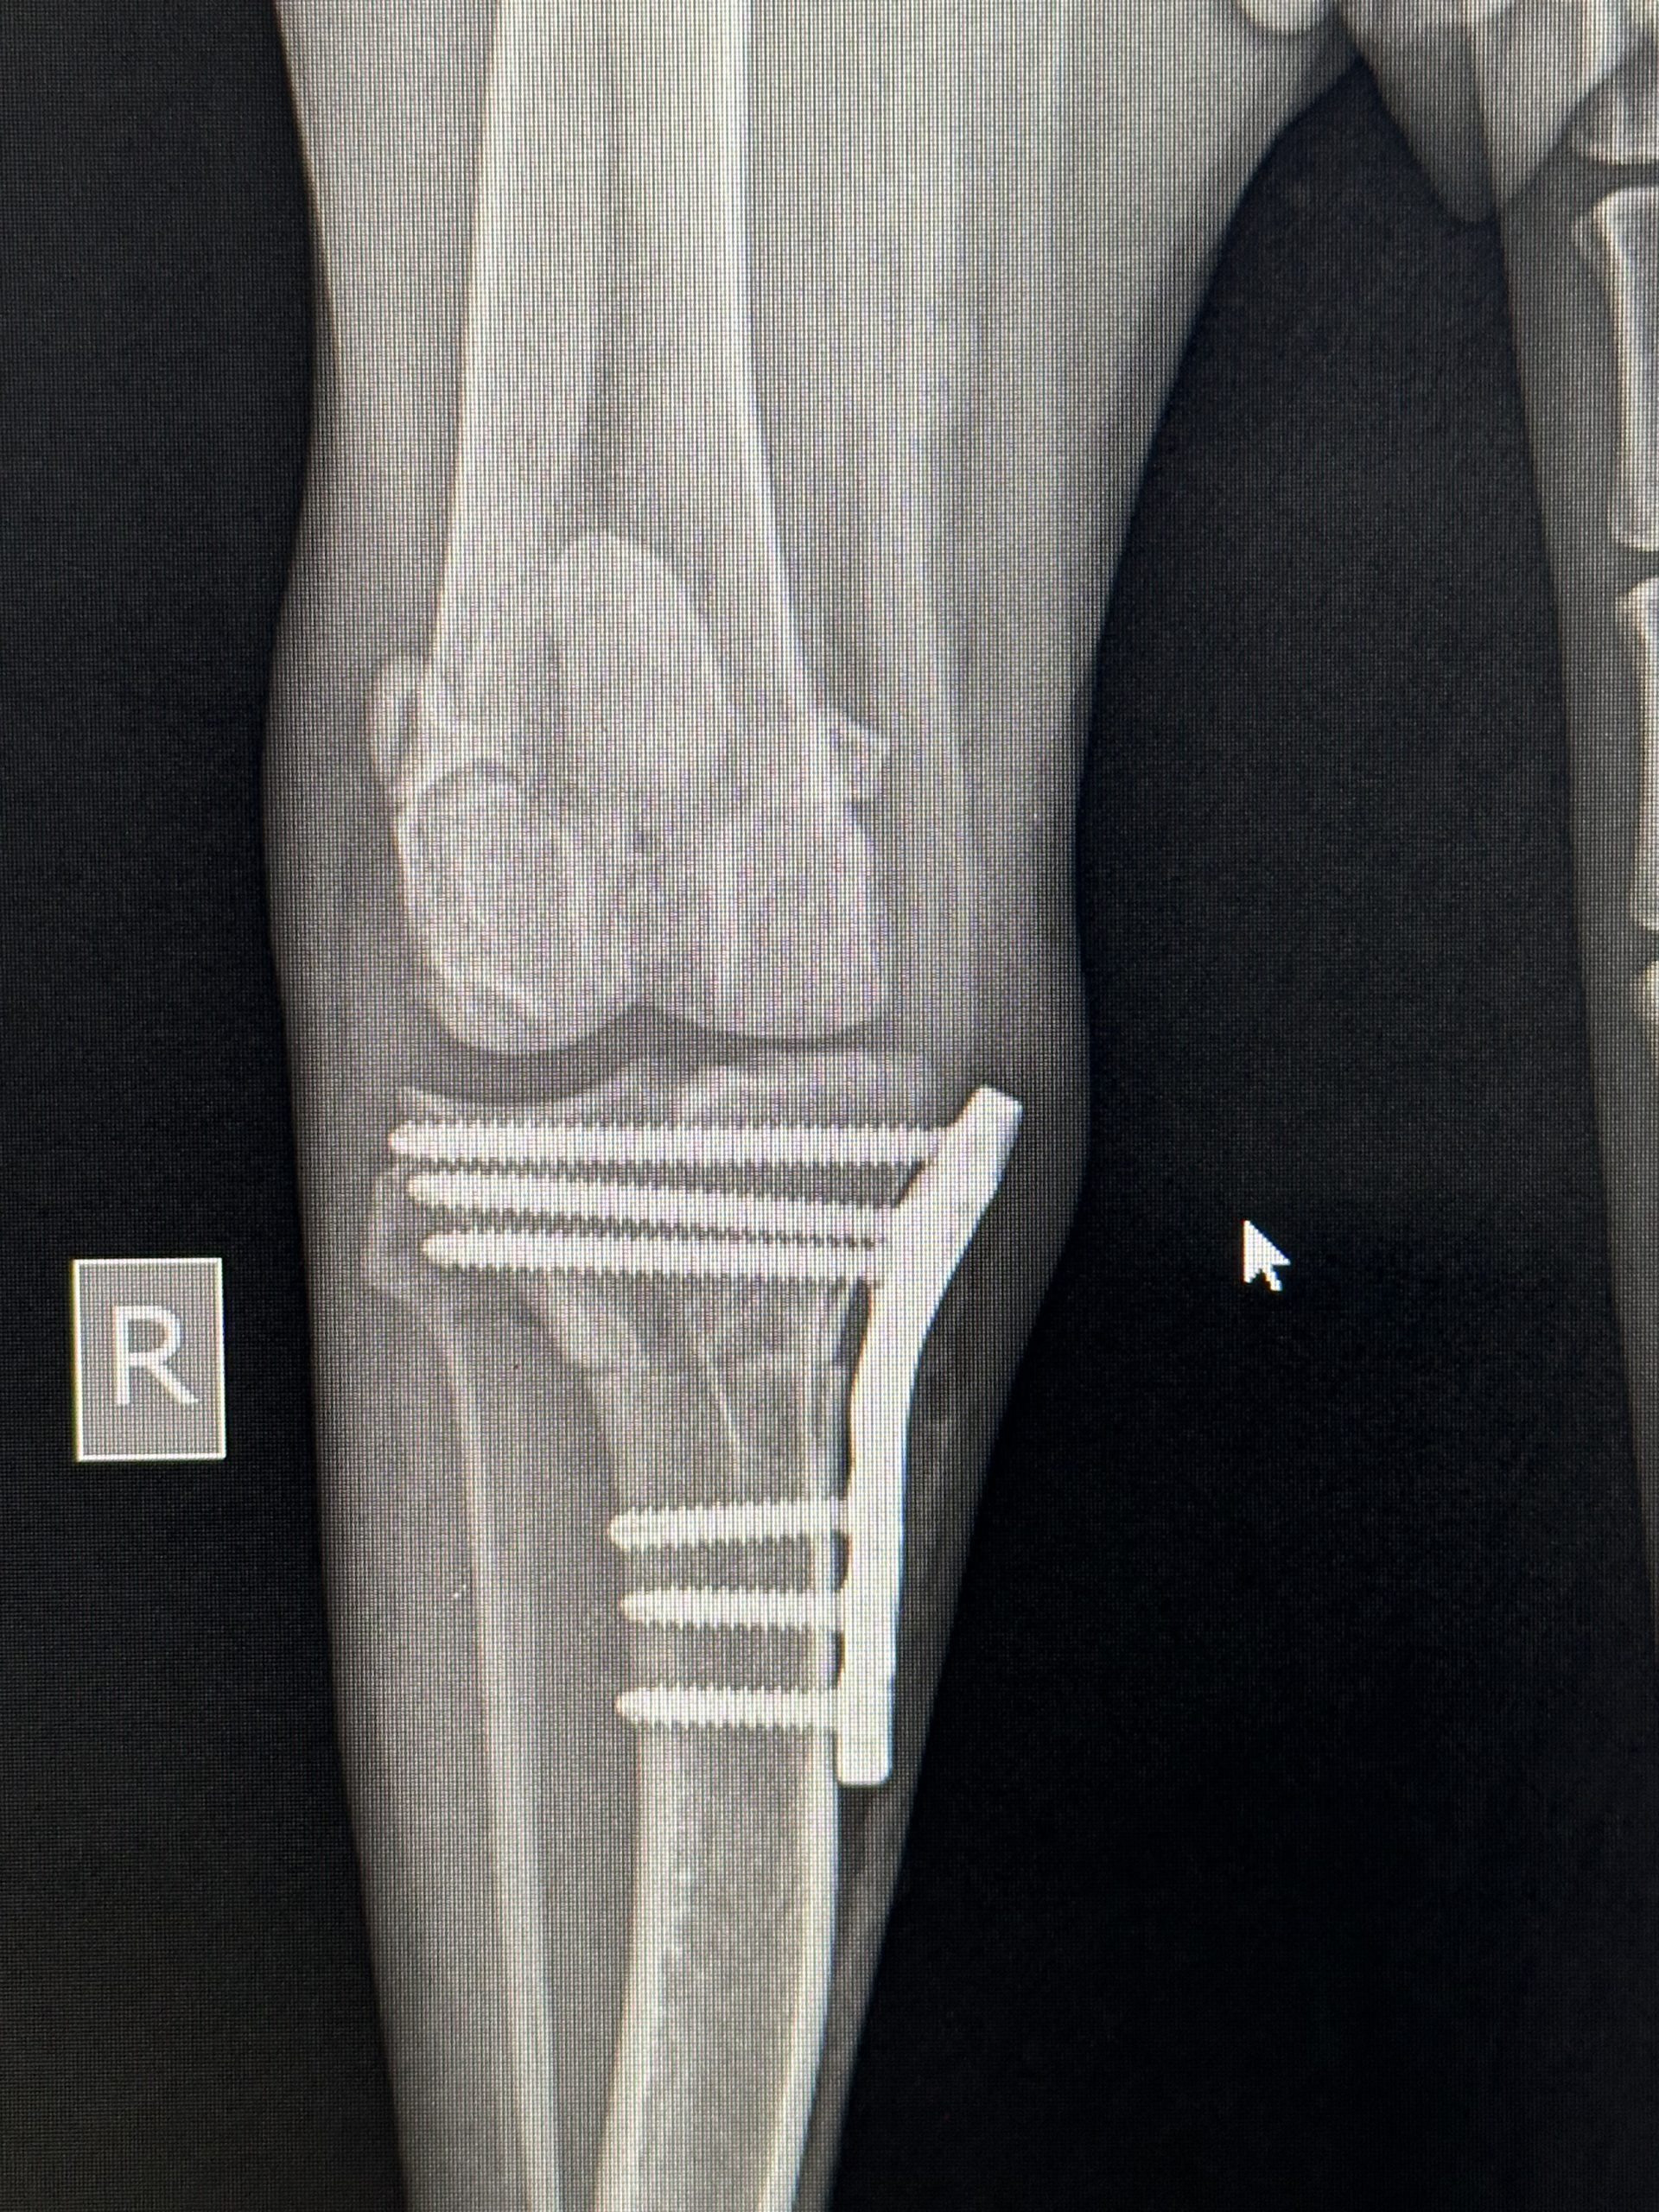

Hirurško liječenje rupture prednjeg križnog ligamenta koljena - TPLO

Za razliku od tradicionalnih metoda koje pokušavaju zamijeniti ili rekonstruisati ligament, TPLO mijenja biomehaniku koljena. Tokom zahvata, hirurg reže tibijalnu ploču (gornji dio goljenične kosti) i rotira je pod precizno izračunatim uglom kako bi se smanjio nagib zgloba. Time se eliminira klizanje femura po tibijalnoj ploči, koje nastaje zbog puknuća ligamenta, i stabilizira koljeno bez potrebe za ligamentom.